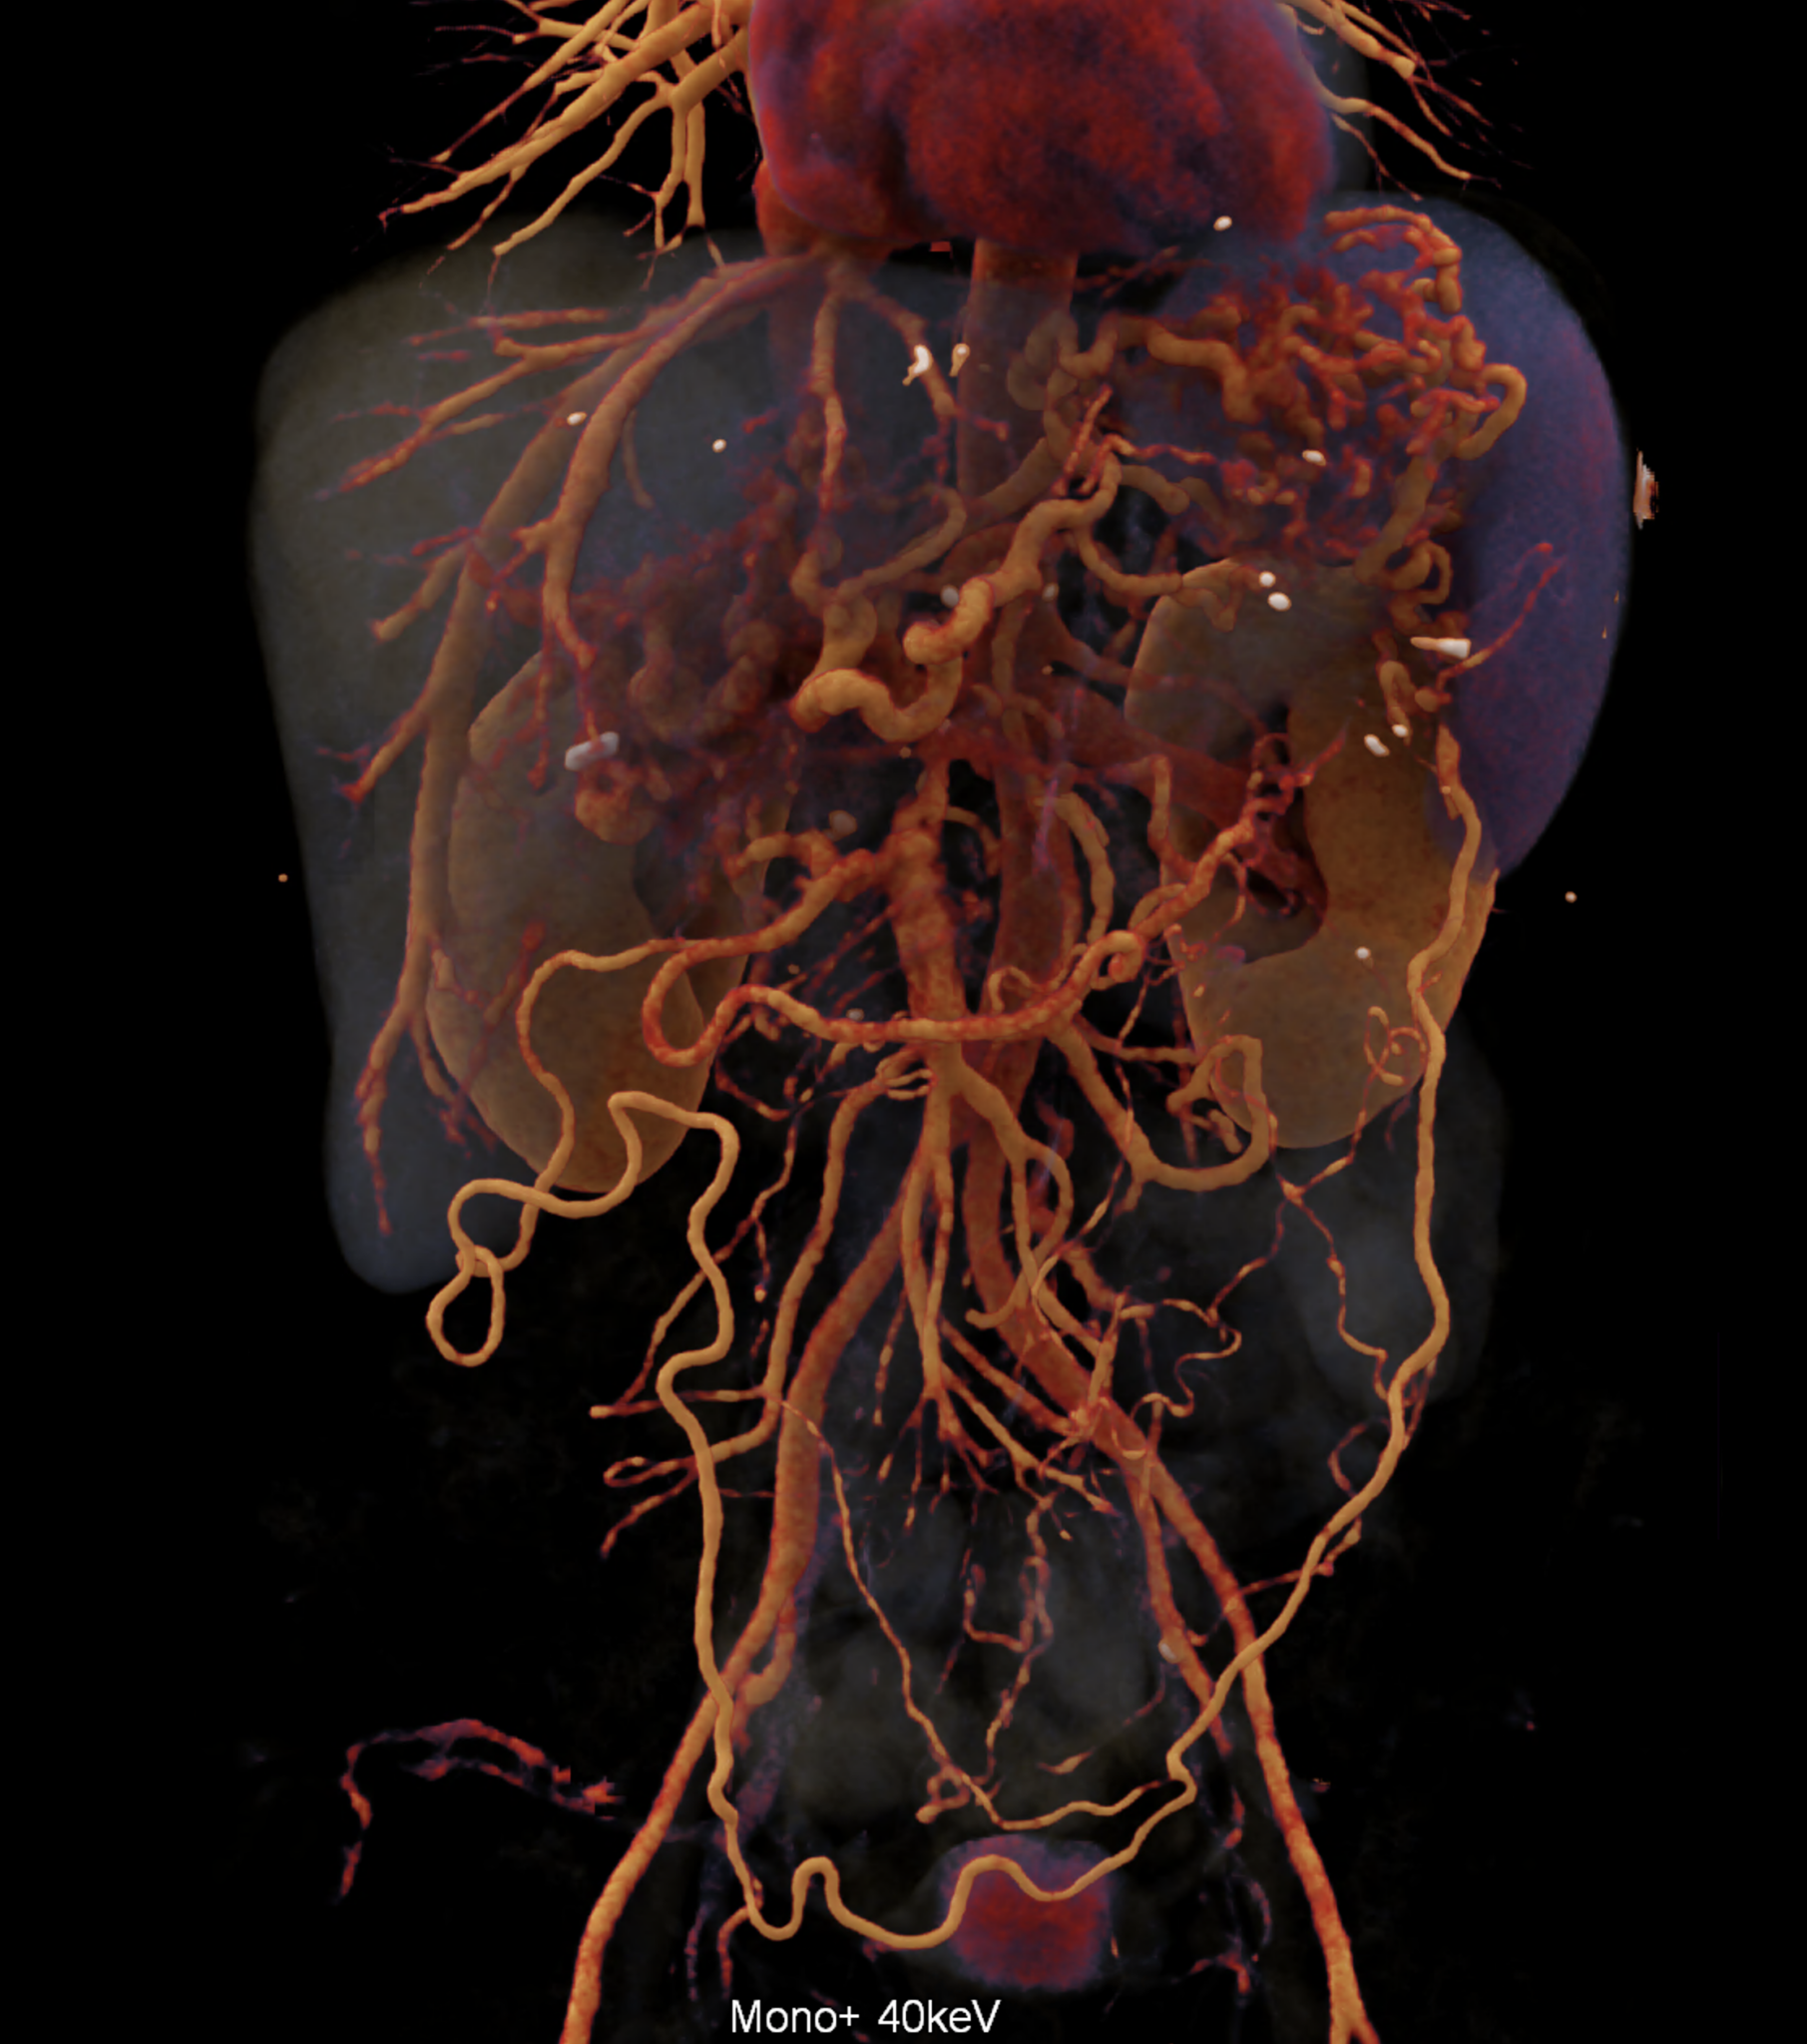

The spectral characteristics of data obtained using photon-counting CT allow optimization of the signal from the venous system, thereby increasing the difference between saturated collaterals and the surrounding area. At the same time, excellent spatial resolution aids in the visualization of bile ducts filled with bile.

A patient with chronic pancreatitis and chronically occluded portal vein. The bile ducts have a significantly dilated wall, from the trunk, through the stump of the cystic duct, to the right and especially the left branch of the hepatic duct. At the same time, a large pseudocyst in the pancreas, dilatation of the pancreatic duct, and chromic occlusion of the superior mesenteric vein, splenic vein, and portal vein trunk are evident. Along with portal biliopathy, there is also arixy of the cardia and esophagus, as well as cavernous remodeling of the portal circulation itself.

volume rendered image after bone and kidney removal showing best the portal biliopathy